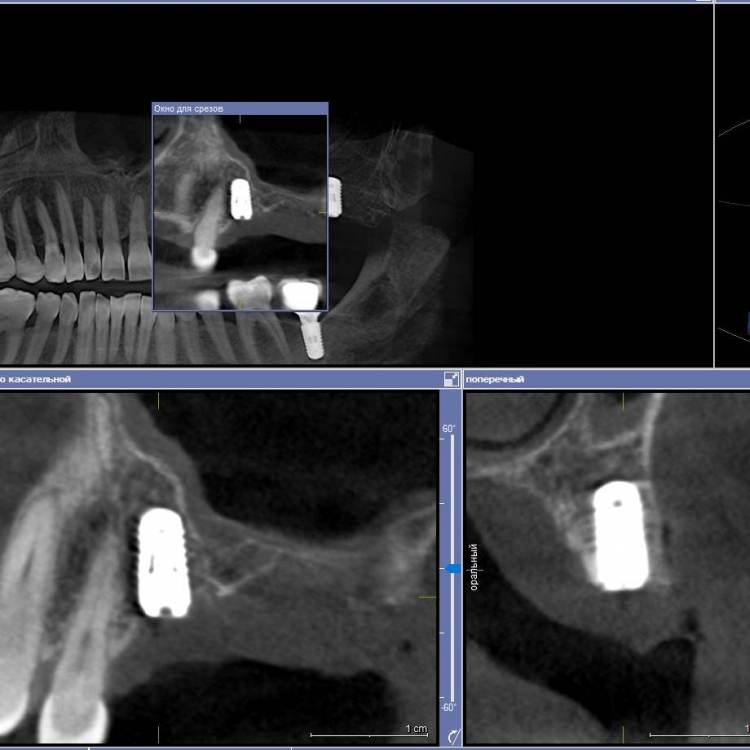

Ponchik Опубликовано 28 апреля, 2021 Поделиться Опубликовано 28 апреля, 2021 Добрый день. Показываю мой новый опыт ? для многих на форуме это рутина, но может кому-то интересно(полезно) будет. 1. Сделано КЛКТ, в GalileosViewer примерное планирование из расчёта избежать синуслифтинг (очень против пациентка). 3.7 на КТ моя работа два года назад. Выявлен новый кариес на дистальной у 3.6. 2. Сделал скан на primescan 3. Планирование далее в другой лаборатории. Наш техник пока не смог в 3д принтер (Надо самому освоить) Пришлось долго переписываться. Так как в дайкомоских файлах нет оказывается плана на имплантацию. Он не передаётся. 4. Изготовили и доставили шаблон. 5. Итоговая работа - 2.5 - штрауманн бл 4.1-8 2.7 - штрауманн бл 4.8-8 с небольшим поднятием остеотомом дна. Поднимал даже не стуча, продавилось остеотомом. Замечания: шаблон сел хорошо, особенно когда отломились резцы ))). Обговорить поперечные балки с техником я не догадался и на резцах шаблон и заканчивался. Дистальная часть заметно двигалась вверх, вниз. Вставить фрезу с надетым шаблоном, нереально в области 2.7, 2.8. рот так не открывается (эх, был бы это Мик Джагер) попробовал втавить фрезу в шаблон, а потом наконечник прищёлкнуть, не смог. Всё равно не влезть. поэтому дистальная втулка использовалась как направляющая для грифеля карандаша. Ну хоть так шаблон, но помог. Передняя втулка довольно легко выдвигалась. Не подклеивал ни как. Вывод: не смотря на неудобства, считаю шаблон мне очень помог. Учитывая огромную толщину слизистой и хз как я бы там на глаз наставил. А так даже без вертикальных разрезов работал. 3 2 Ссылка на комментарий